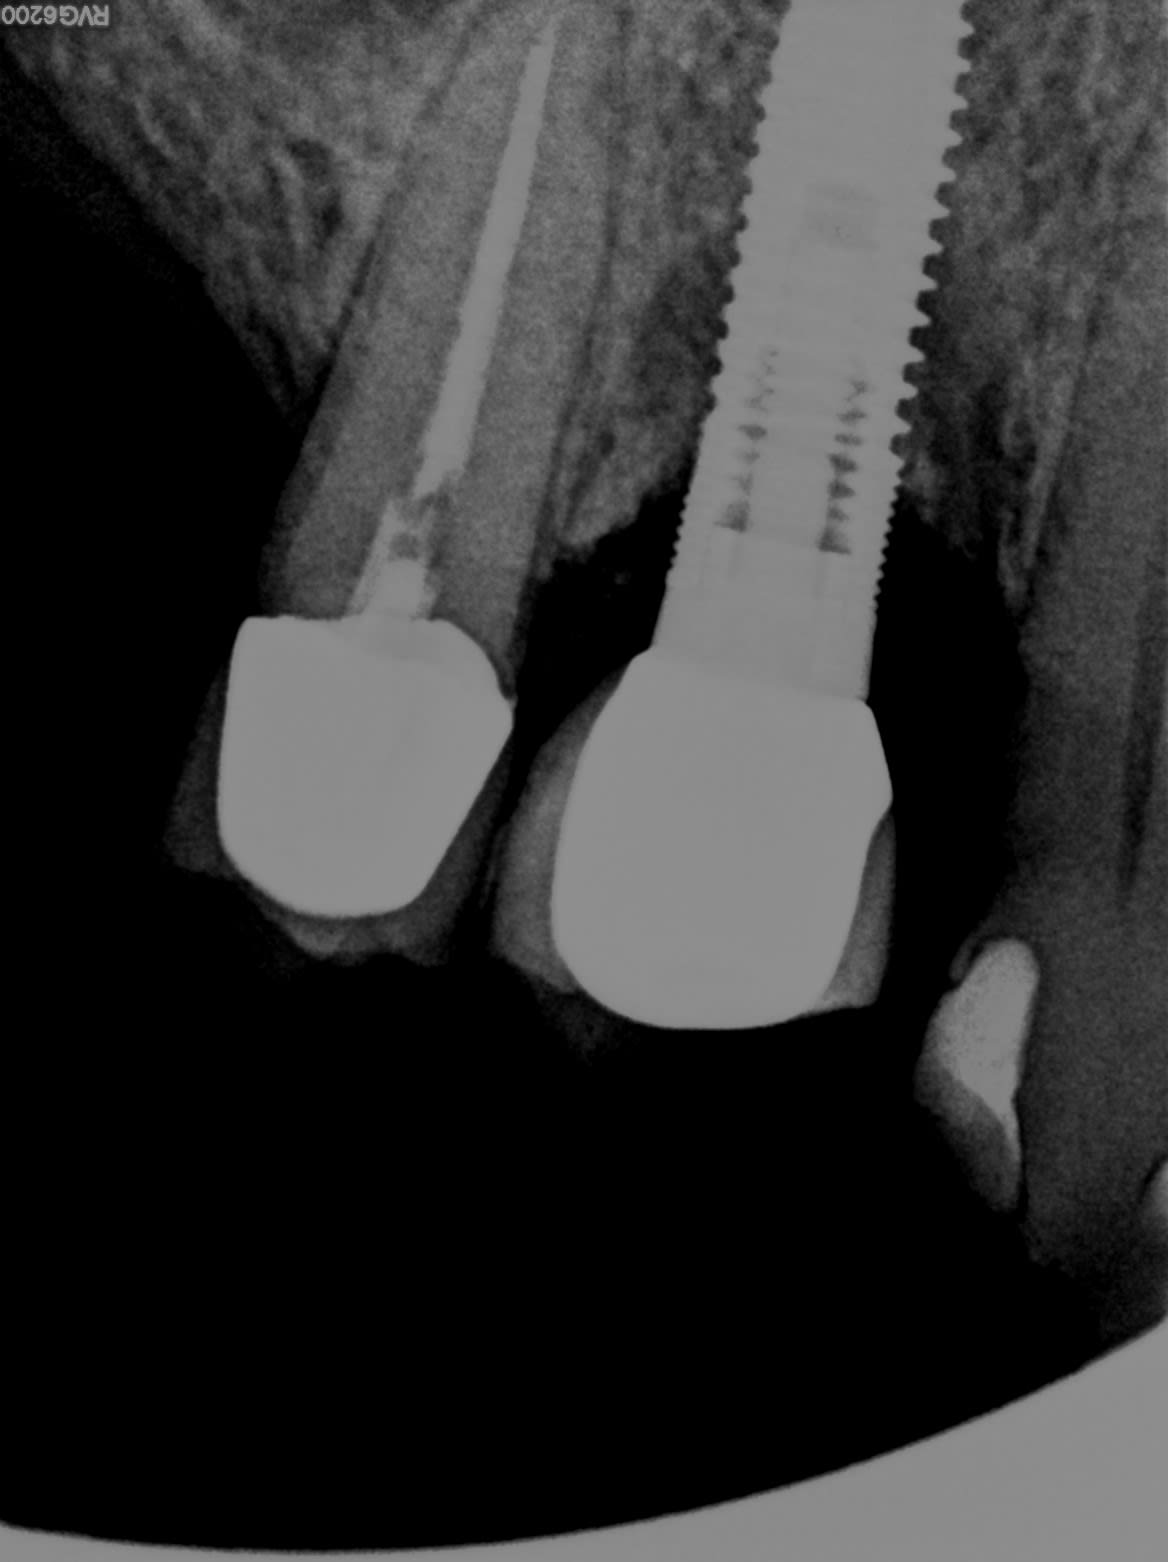

En attendant voici une autre radio recontrastée

Ça pourrait être un Nobel replace trilobe.

Sur la seconde radio le col de l’implant semble fracturé.

Oui je pense que cela peut être une fracture.

Le patient décrit une mobilité et des symptômes inflammatoires dans la zone.

L’inflammation me semble sauter aux yeux sur la première radio, mais c’est pas ma partie ☝️

Honnêtement, je n'avais pas vu la fracture sur la première radio transmise

J'ai pu voir le patient.

Je n'ai pas retrouvé de fracture finalement.

Je vais ouvrir pour voir si le sauvetage est jouable ou si tourne a gauche.